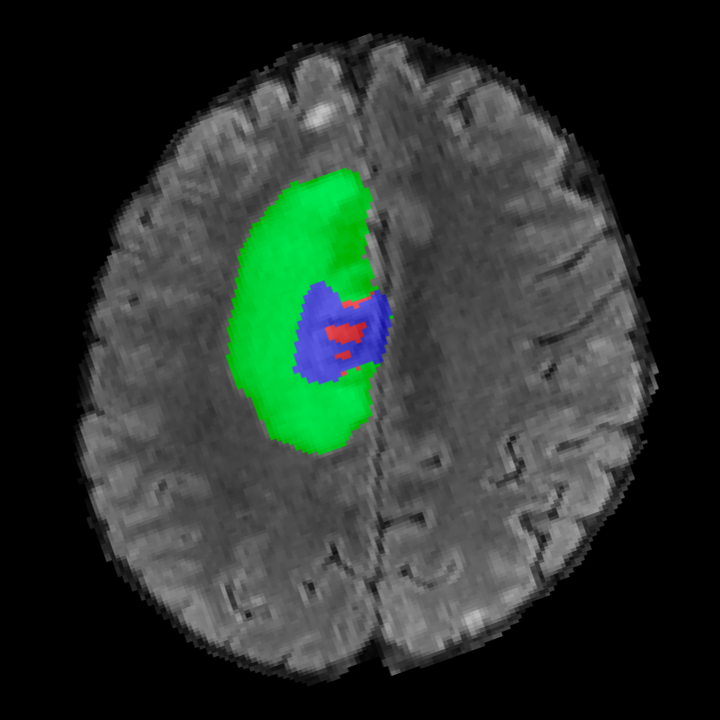

Tumour Information Preservation. For the brain tumor segmentation, we use a Swin UNETR model[28, 70], trained with random rotation, and intensity as data augmentation. On the test set with human ground-truth annotations (), the brain volumes generated from single slice input preserve the volume of the different tumour components (paired t-test, for all 3 classes). In Figure 4, we highlight the tumor profiles of the generated MRIs compared to the ground truth tumour profile. The real MRI Dice score in the test set is 85.15 while the generated MRIs from a single slice have a dice score of 83.09. This shows how the generated MRIs indeed preserve the tumor information and can act as an affordable and informative pseudo-MRI, before conducting an actual costly MRI examination in hospitals. More detailed results are provided in supplementary material.

On the test set with human ground-truth annotations (), the brain volumes generated from single slice input preserve the volume of the different tumour components (paired t-test, for all 3 classes) (see Table I). The real MRI Dice scores are put for reference to our generated MRIs. X-Diffusion outperforms baselines TPDM [39] and ScoreMRI [19] in tumour preservation (see Table I and Figure III). We ran experiments comparing the tumour segmentation Dice Score varying X-Diffusion configurations. The multi-slice input X-Diffusion achieves marginally better Dice Score than the single slice input model (83.47 83.09). We also ran experiments with slice input used for volume reconstruction intersecting or not with tumour. We observe on average a drop of 6% Dice Score (see Table I). Further away from the tumour the input slice for volume reconstruction is selected, we observe a linear decrease in tumour segmentation Dice Score with lowest value of 77.21 Dice Score (see Figure VI).